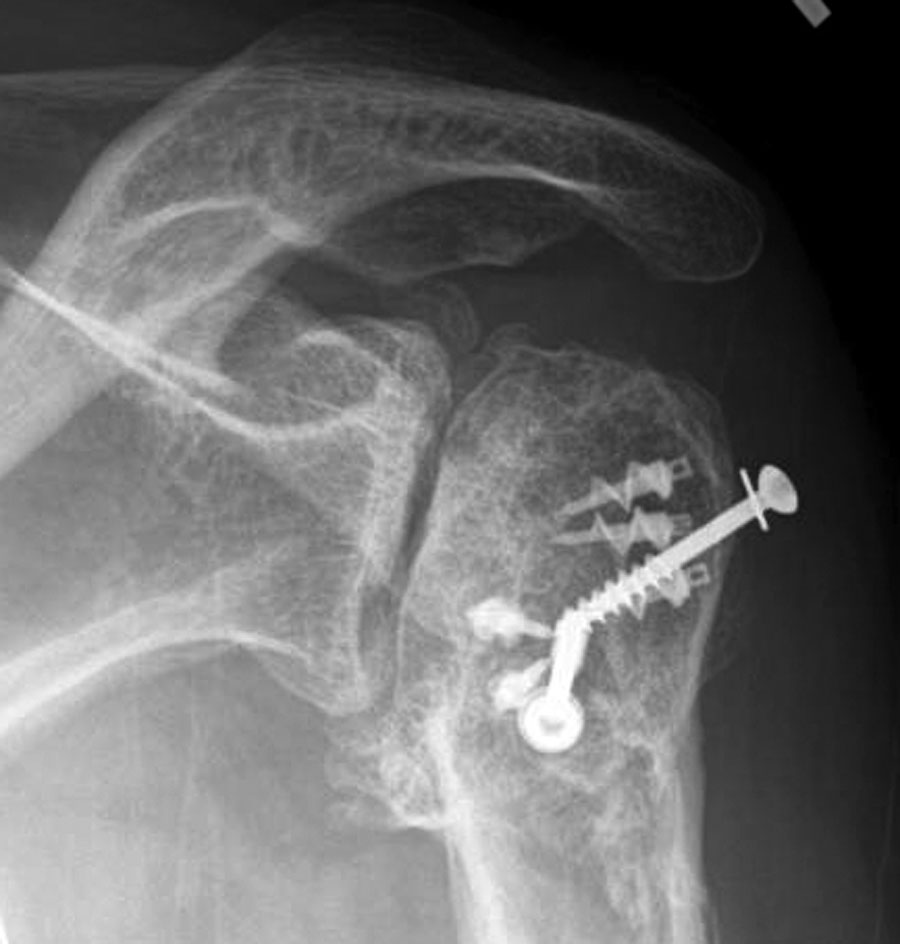

UW Shoulder and Elbow Academy Post traumatic arthritis of the shoulder